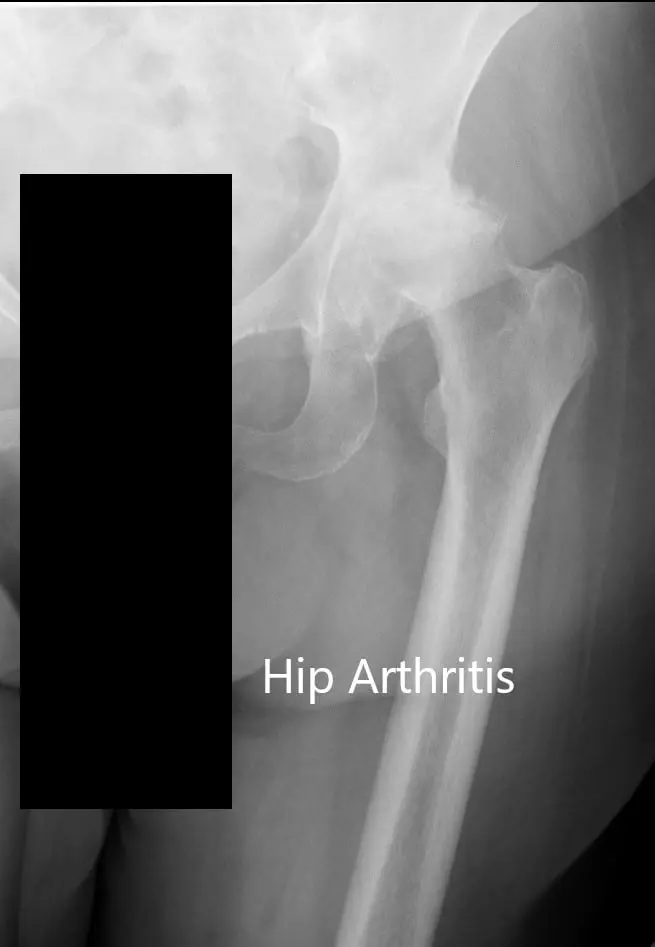

Imaging studies revealed bilateral hip osteoarthritis which was severe in the left hip with dysplasia of the acetabulum. In view of lifestyle limiting hip pain, he was advised left total hip replacement. Risks, benefits, and alternatives were discussed with the patient at length. The patient agreed with the plan.

Preoperative X-ray of the left hip showing AP and lateral views.